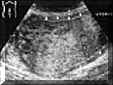

Diagnosis

in

Second

Trimester:

The

sonographic

findings

of

hydatidiform

mole

are

distinctive

and

characteristic.

enlarged

uterus

is

filled

with

echogenic

material,

numerous

sonolucent

vesicles

various

size

interspersed

within

it

(Picture1).

Picture1.

Complete

trimester.